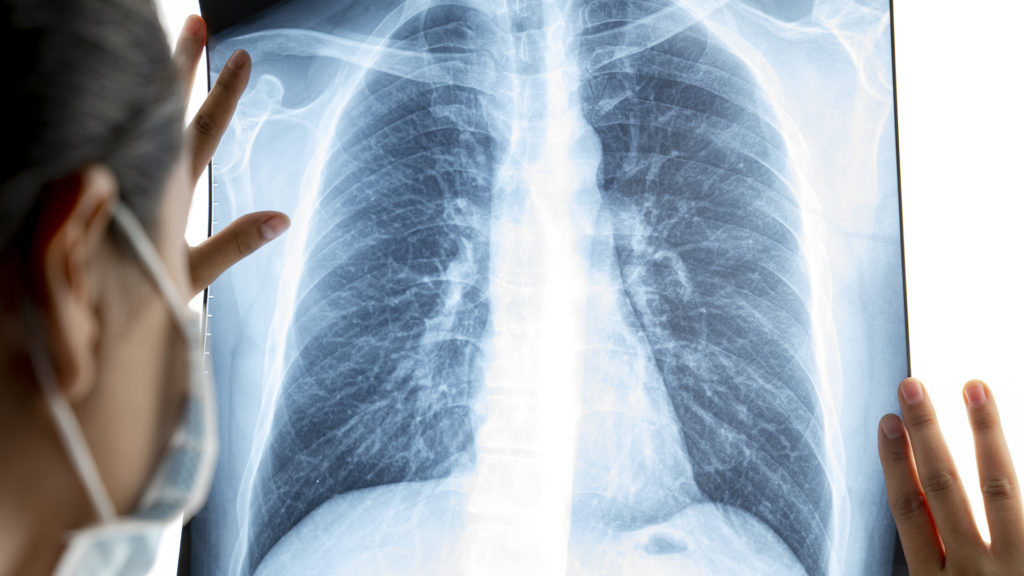

A koronavírus-fertőzés komoly szövődményeket okozhat a tüdőben (Fotó: Getty Images)